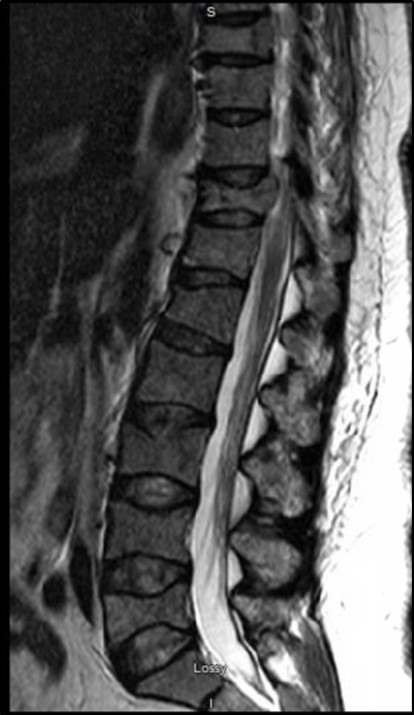

Fifty-seven-year-old female with a history of hypertension presented with progressively worsening shoulder and back pain. Physical exam was significant for diffuse bone tenderness. Bone skeletal survey showed multiple punched out lesions (Figure 1A, Figure 1B), diffuse demineralization and compression fracture in T12 and L1. Laboratory findings were significant for anemia (hemoglobin 6.2 g/dL) with peripheral blood smear revealing rouleaux formation, hyponatremia 126 mmol/L, elevated creatinine 3.23 mg/dL with blood urea nitrogen 45 mg/dL, albumin of 3.1 g/dL, hypercalcemia 15.5 mg/dL (corrected calcium 16.2) and marked hyperphosphatemia 20.5 mg/dL. Patient had high serum viscosity 3.1 centipoises, elevated total protein levels 11.9 g/dL, elevated IgA 4598 mg/dL, low IgG 580 mg/dL and low IgM 24 mg/dL. Inorganic phosphorous measurements on deproteinized serum samples revealed normal phosphorous levels. Parathyroid hormone and 25-OH vitamin D levels were normal. An increased AG of 24 was observed after correcting for albumin. An electrocardiogram revealed osborn waves in the setting of severe hypercalcemia. Serum, urine protein electrophoresis and bone marrow biopsy were performed, and she was diagnosed as IgA kappa type mutiple myeloma. MRI spine revealed rostrocaudal cord edema spanning T10-T12 secondary to significant cord compression requiring emergent intravenous steroids (Figure 2). Patient was managed with intravenous fluids and pamidronate for hypercalcemia. Due to refractory nature of hypercalcemia patient required urgent hemodialysis.

Figure 2.Several pathologic compression and burst fractures throughout the spine. Ventral cord indentation at T1, T8 and T11. Rostrocaudal cord edema spanning T10-T12 secondary to more significant cord compression. Bulky left paraspinal osseous/extraosseous disease at T8 (arrow) causing potential impingement.